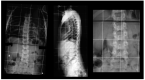

(1) Background. Scoliosis is the most common musculoskeletal manifestation of Neurofibromatosis type 1 (NF1), and it might be dystrophic (D) or non-dystrophic (ND) depending on the presence of dysplastic changes of the spine. The aim of our study was to describe the characteristics and natural history of patients with NF1 and scoliosis. (2) Methods. We retrospectively reviewed records from patients with NF1 and scoliosis. Scoliosis was classified as D if at least two dystrophic changes were documented at imaging. (3) Results. Of the 438 patients reviewed, 43 fulfilled inclusion criteria; 17 were classified in D group and 26 in ND. The groups did not differ in age and localization of scoliosis curvature. Surgery was needed more often in D group, but the between-group difference was not significant. Male-to-female ratios of 3:1 and 4:1 were reported in surgically treated NF1 patients with ND and D scoliosis, respectively. (4) Conclusions. Our data suggests independently by the presence of dysplastic changes affecting the spine that males with NF1 are more often affected by scoliosis that requires surgery.